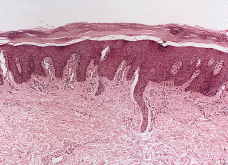

FIG. 5.--Biopsia cutánea tomada a los 17 años de edad. Existe hiperqueratosis ortoqueratósica compacta, atrofia de la granulosa con áreas de paraqueratosis, acantosis psoriasiforme e hiperplasia vascular dérmica superficial.